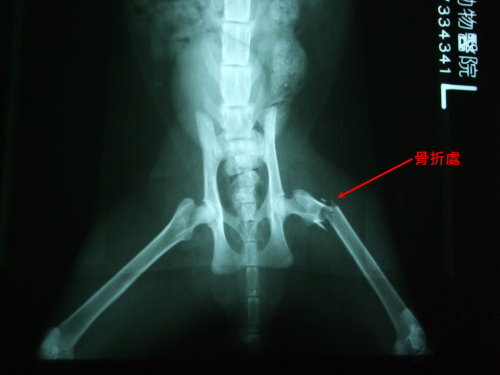

主題: 狗嘴逃生的骨折黑貓 申請者姓名: 蔡葦澄 花色: 申請日期: 2012-07-15 21:07:44 申請者部落格: 申請者臉書網址: 所在縣市/合作醫院: 台北市/澄毅動物醫院 治療費用: 20350元 需求人數: 23人 已結案 (2012-12-01 22:05:16) 報名人員: Anita Wu(已付款)、Jamie(已付款)、Ku-ai Gina Chen(已付款)、Hsin-Yi Chiao(已付款)、蘇圓容(已付款)、艾薇拉(已付款)、viki(已付款)、Claus(已付款)、艾薇拉(已付款)、鳳公主(已付款)、丁小乖(已付款)、無名氏(已付款)、Kent(已付款)、Aaron Liu(已付款)、Minling(已付款)、Ju-jan Hsu(已付款)、sama05(已付款)、陳淑娟(已付款)、上官玉喵(已付款)、不不熊、不不熊(已付款)、kelly(已付款)、Vanna Tai(已付款)、小P(已付款)、 候補人員: 藍琉璃、Evelyn H、小舟、 動物病情說明: 聯合報管理員郭大哥通報,有一隻黑貓被一群浪狗攻擊,叼起來重摔在地,貓躲進大樓垃圾場,平時不方便給外人進出,於是教導郭大哥使用誘捕籠,捕抓後緊急送至動物醫院,X光確認貓咪後腿骨折,手術接回斷骨(氣麻),術後恢復狀況不錯,因為貓咪很兇開籠門會衝撞,所以盡量不去探視驚擾,數日後貓咪開始不吃不喝,瞇瞇眼、淚水量多,似呼吸道疾病,又有輕微脫水,於是上點滴五天後狀況比較穩定,拆點滴投以抗生素治療,因為斷骨需時間復原癒合,住院期間為避免感染貓瘟,於是施打疫苗,貓咪癒後良好,擇日放回。目前仍由郭大哥繼續於原地餵食,健康狀況良好。還請各位能幫忙狗嘴逃生的骨折小黑的醫藥費。